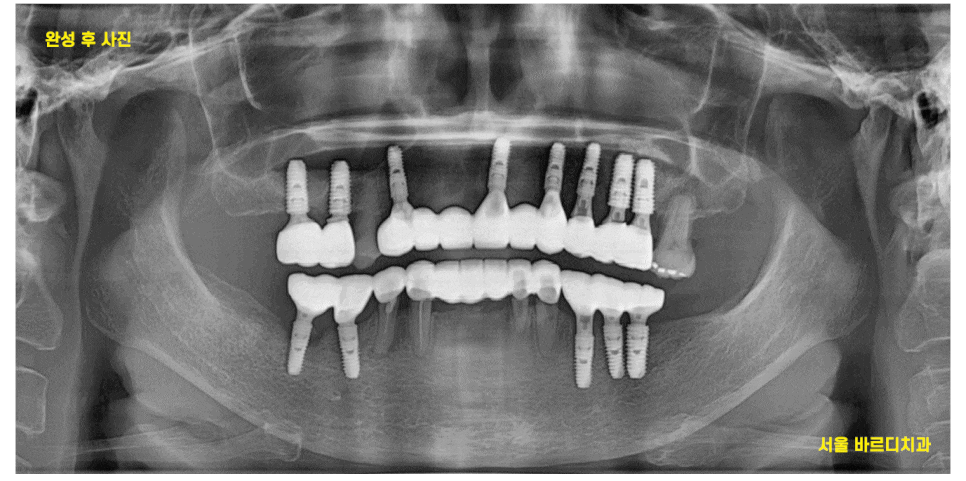

암사동 치과 전악 임플란트 하루만에 끝냈습니다.

하루에 위, 아래 임플란트 수술을 진행했습니다.

24.04.30

가이드를 통해

빠르고 정확한 수술이 가능했지만

개수가 많다보니 초집중

디지털 장비를 사용한 꼼꼼한 분석으로

전악 임플란트 하루만에 끝낼 수 있습니다.